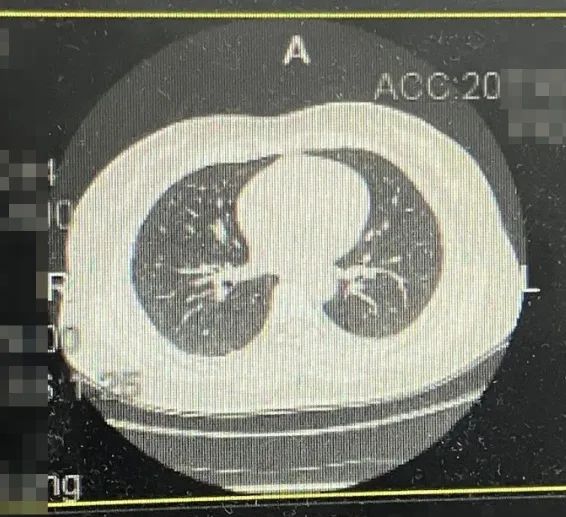

·CT

1、右乳后上方结节影,伴右侧腋下多枚淋巴结,建议乳腺核磁MRI平扫+增强进一步检查;

2、右肺下叶及左肺下叶胸膜下少许间质增生,或可能由肺坠积效应所致;

3、肝脏钙化灶

4、胸腰椎轻度退行性变。

图4 CT结果